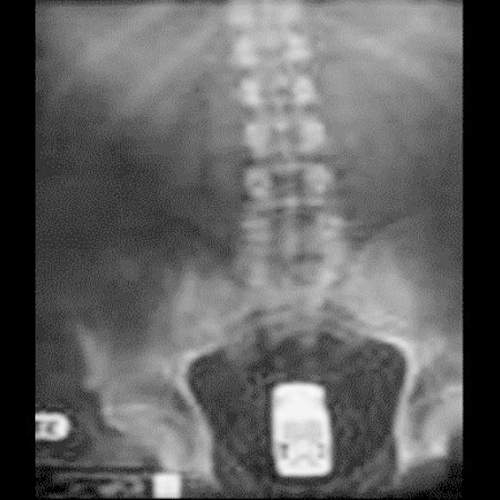

這張異物突入X光照當中的物體是花生醬瓶~但你應該不會感興趣裡面有沒有花生醬